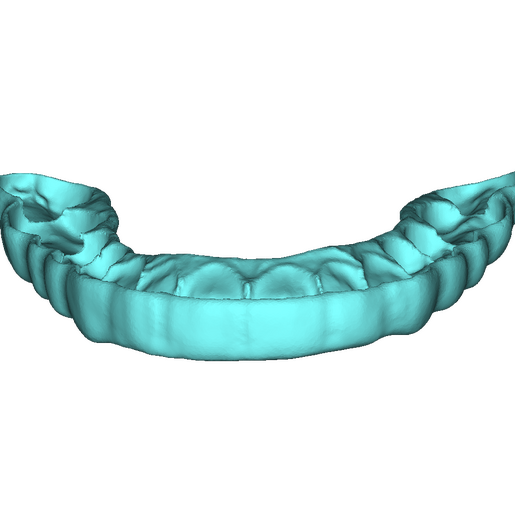

DSD Bite Splint Design

The DSD Bite Splint (night guard) is designed to be worn after a full mouth rehabilitation to protect DSD Natural Restorations and/or DSD Direct composite restorations. The splint design can be used for both milling and printing.

This product is ideal when you need to protect restorations that have already been placed to help avoid possible fractures due to grinding and bruxism.

This is a digital product, delivered in STL format.

An .STL file of the DSD Bite Splint design that can be used for manufacture, either by DSD Lab or your local lab.